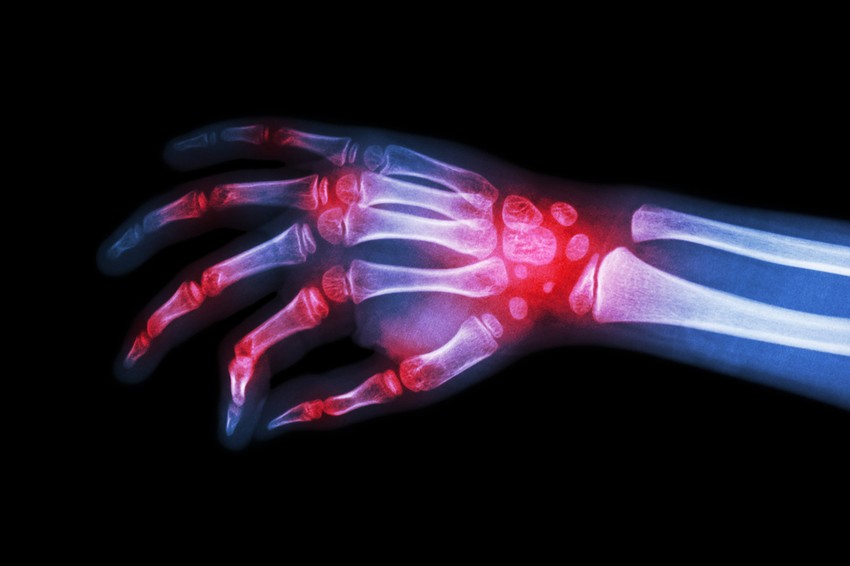

Az artritisz szó maga az ízület gyulladását, gyulladt állapotát jelenti. Legjellemzőbb tünetei a fájdalom, az ízület merevsége, és időnként duzzanata is.

Az izületi fájdalmak merevséget okozhatnak.

Az izületi gyulladás duzzanatot okozhat